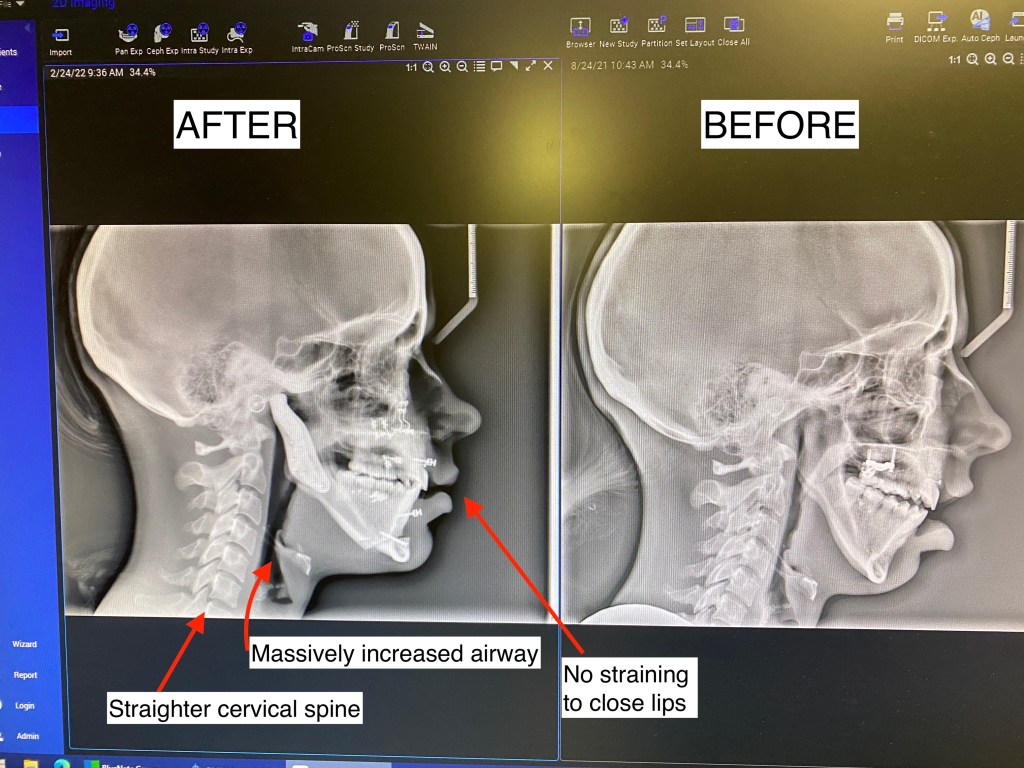

It has been a FULL WEEK since my surgery!! It feels like it has gone by so fast! First off, I want to start this post by showing my first before and after Xray which I couldn’t be happier about!! Look at that airway. I am so thankful now that this surgery was an option for me. I spent a long time rightfully being scared of it, but did the amount of research I felt comfortable with and felt like I knew my own personal pain / TMJ issues well enough going into it to to decide for myself if I thought it would give me a better shot at living. It took me a full year to fully research, consult with 4-5 different jaw surgeons, and talk with anywhere from 100-200 patients online (I’m not even kidding. I am very careful with my health and decisions after what happened to me in the past with jaw treatments and extreme orthodontic work). I was talking with one of my good ICR friends a while back who also researches a lot and we kind of laughed that we envy the people who go into this blind and just get perfect results. No worry or anxiety.

- Forward Head Posture/ cervical spine: As the mandible dips back from ICR, it presses on the airway causing the head to tilt forward and the neck to crane in order to open up the soft tissue of the airway enough to receive adequate oxygen. I’m so thankful the body adapts, but these adaptations are not without consequences and many of the consequences we still don’t medically have a good grasp on to know just how far reaching they are to other systems in the body.

- My post op x-ray shows a straighter head posture! I have been seeing a chiropractor the past few years to help manage some of my chronic pain, so I imagine he will be very happy to see this!

- Lips are closed: It is HEALTHY to breathe through the nose and to have your lips closed. Those with ICR are unable to do this without muscle strain, which encourages mouth breathing. Mouth breathing causes all. kinds. of. problems. You can read more about them here if you are interested: https://www.endur.com/blogs/blog/8-scary-consequences-of-mouth-breathing